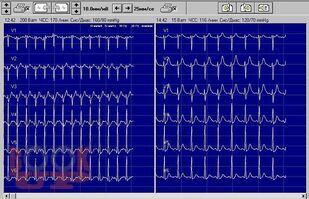

Пробы с физической нагрузкой (велоэргометрия, тредмил-тест)

В учебном пособии представлены современные подходы к методу нагрузочного тестирования и сведения, которыми необходимо обладать для самостоятельного проведения велоэргометрии и тредмил-теста.

Пособие предназначено для проведения лекционных, семинарских занятий и самоподготовки обучающихся в клинической ординатуре, слушателей курсов первичной переподготовки, а также на циклах повышения квалификации по дисциплине «Кардиология», специальности «Функциональная диагностика».